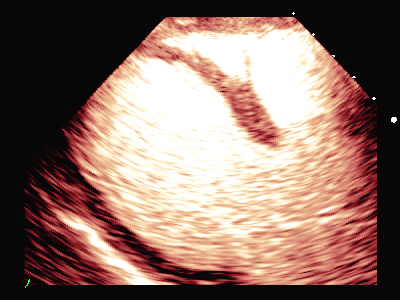

图(1)

图(2)

冠脉CTA:左前降支近端多发软硬斑块形成,管腔狭窄约80%。